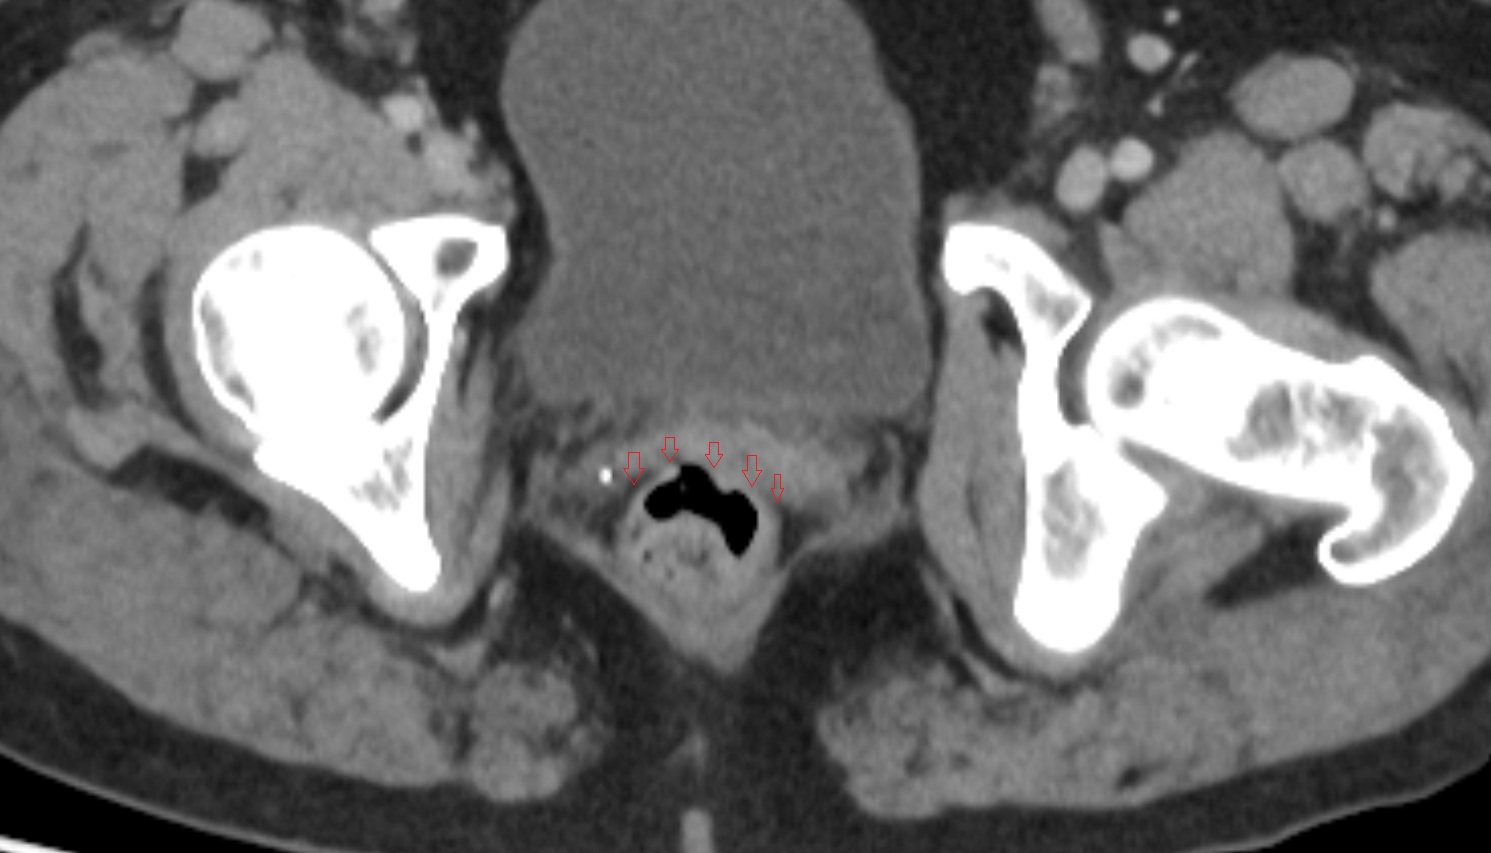

- Urinary bladder

- Uterus

- Vagina

- Ovaries